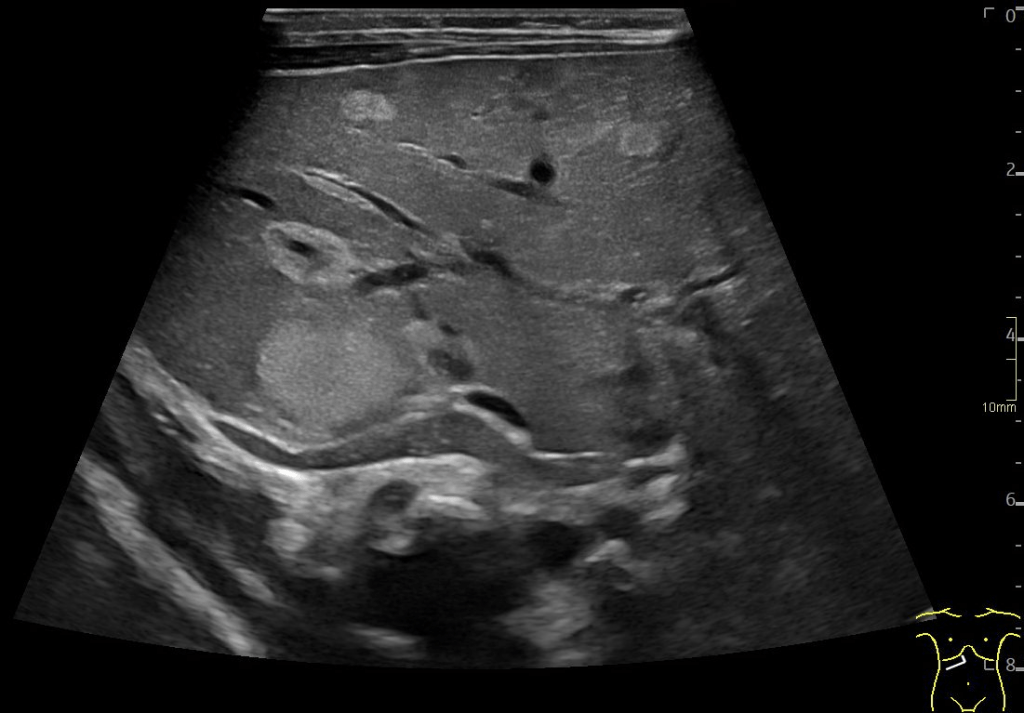

A: B-Mode image in the axial plane demonstrating multiple hyperechoic, well-defined lesions in the liver. Other lesions demonstrate a hypoechoic central area.

Multiple hepatic lesions were identified on ultrasound (A). Some lesions appeared as typical, well-defined hyperechoic cavernous hemangiomas (2), while others demonstrated large, tortuous vessels. Additional lesions showed a hyperechoic rim with a hypoechoic center and internal Doppler flow, consistent with capillary hemangiomas (2). In some HH (B), arteriovenous shunting was suspected. However, Triplex Doppler examination demonstrated normal hepatoportal flow in the portal vein (C) with flow velocities below 40 cm/s – within the normal range for the age – as well as a normal triphasic flow pattern in the hepatic veins (D).